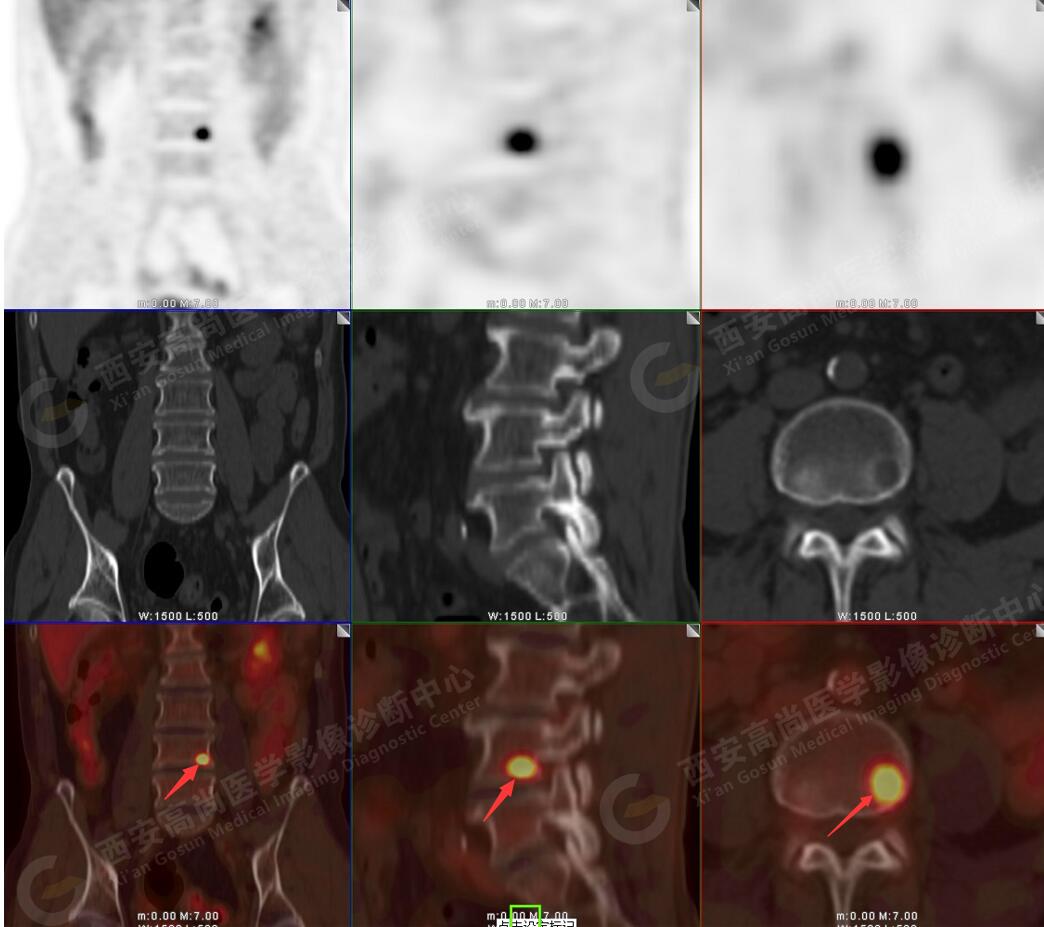

5.腰4椎體左側緣溶骨性骨質破壞,FDG代謝異常增高,考慮骨轉移瘤。

以上病變符合:T4N3M1c,ⅣB期(UICC/AJCC,2018年第8版肺癌TNM分期)。